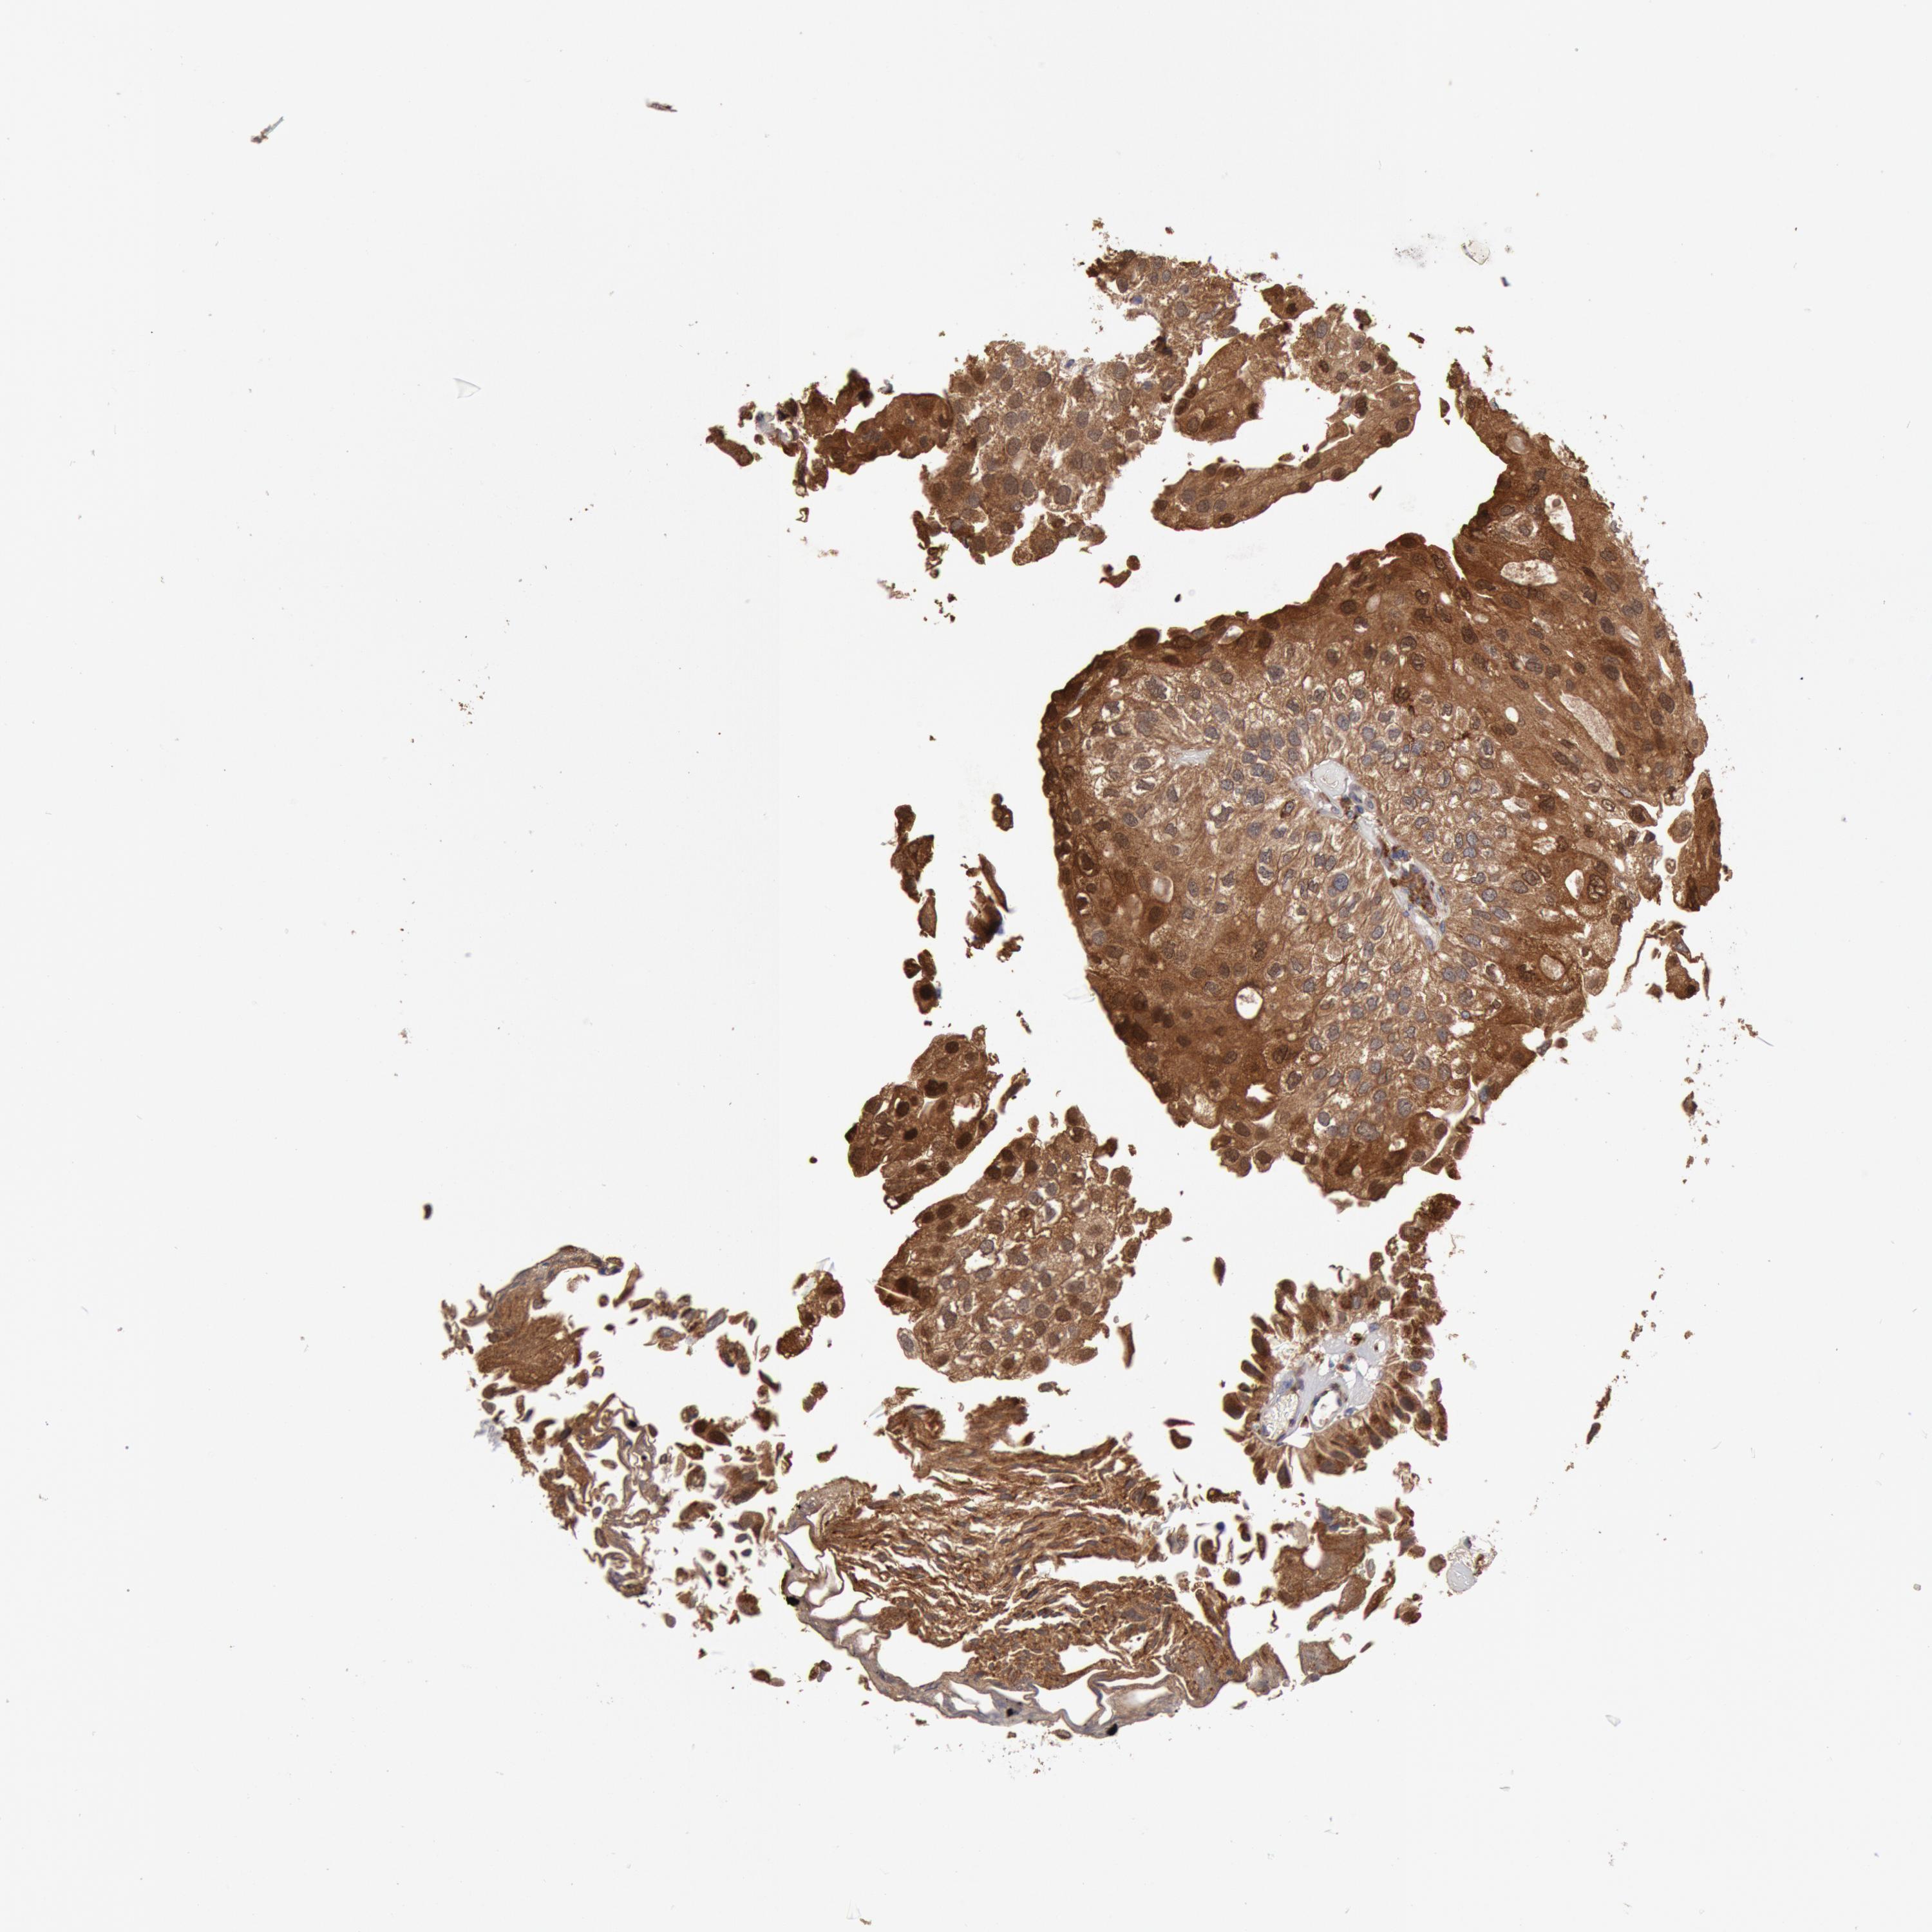

UROTHELIAL CANCER - Protein expressioni

A mouse-over function shows sample information and annotation data. Click on an image to view it in a full screen mode. Samples can be filtered based on level of antibody staining by selecting one or several of the following categories: high, medium, low and not detected. The assay and annotation is described here.

Note that samples used for immunohistochemistry by the Human Protein Atlas do not correspond to samples in the TCGA dataset.

Antibody stainingi

Antibody staining in the annotated cell types in the current human tissue is reported as not detected, low, medium, or high, based on conventional immunohistochemistry profiling in selected tissues. This score is based on the combination of the staining intensity and fraction of stained cells.

Each image is clickable and will lead to virtual microscopy that enables deeper exploration of all samples and also displays staining intensity scores, fraction scores and subcellular localization as well as patient and tissue information for each sample.

Antibody HPA001318

Staining

High

Medium

Low

Not detected

Intensity

Strong

Moderate

Weak

Negative

Quantity

>75%

75%-25%

<25%

None

Location

Nuclear

Cytoplasmic/membranous

Cytoplasmic/membranous,nuclear

Urothelial carcinoma, Low grade